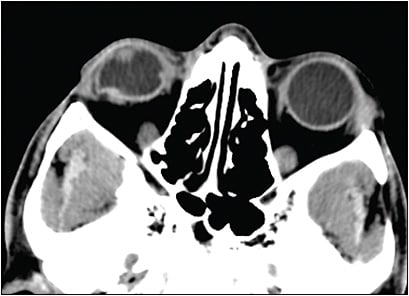

The timing of RD repair after OGR is controversial.33-37 The best time for intervention for RD repairs may be 7 days to 15 days after injury, because this creates an opportunity for the open globe wound to heal, for inflammation to subside, and for initiation of spontaneous posterior vitreous detachment if none was present at presentation.6,23,38 Proliferative vitreoretinopathy may begin to develop and progressively increase within 2 weeks to 6 weeks of injury in presence of retinal tears and RD (Figure 1).39 Corneal edema can be severe enough to preclude a view of the posterior pole that would allow retinal surgery. Vitreoretinal surgery sometimes can be delayed until the corneal edema improves. If retinal surgery is deemed urgent or emergent and if the view of the posterior pole is inadequate due to corneal laceration or edema, one may combine penetrating keratoplasty and PPV using a temporary keratoprosthesis intraoperatively.40-42 Severely injured deformed globes with poor anterior segment anatomy may not be candidates for this procedure.43 Endoscopic vitrectomy may be an option in some eyes with anterior-segment media opacities and an inadequate view of the posterior segment. Endoscopic vitrectomy surgery is performed using image projection from the camera in the probe onto a 2-dimensional nonstereopsis monitor. Identification of the exact location of the endoscope probe requires the recognition of normal landmarks within the eye. The ocular structures may be displaced from their normal location in severely injured eyes, and extensive pathology can render this technique challenging.1,43